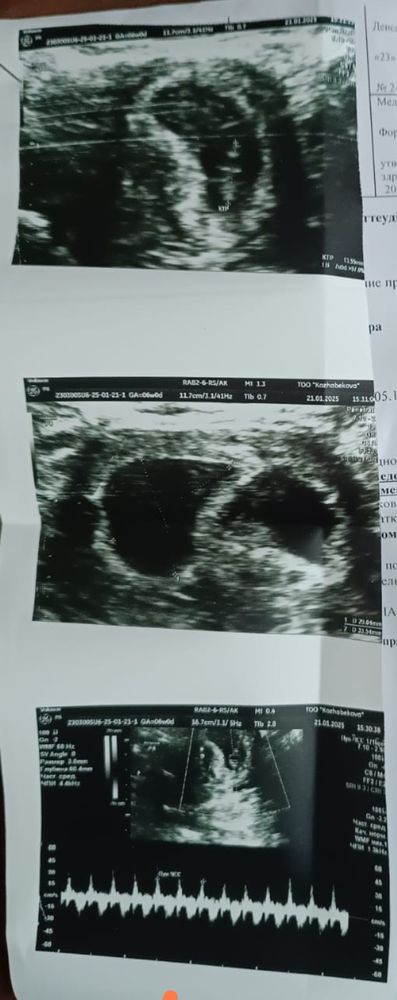

Это УЗИ ре сделала 5+5 дней

Это вчерашний УЗИ врач другой 7 +5 дней

Здравствуйте девочки помогите пожалуйста 7 недель +6 дней беременности эко. Вчера было на УЗИ сказали что гематома, у плода ♥️ есть услышали, когда мне сделала УЗИ 5 недели 5 дней два плодное яйцо было вчера врач ничего не сказала просто сказала что есть гематома леди дома ато будет выкидыш я и так дома лежу ничего не делаю только отдыхаю.